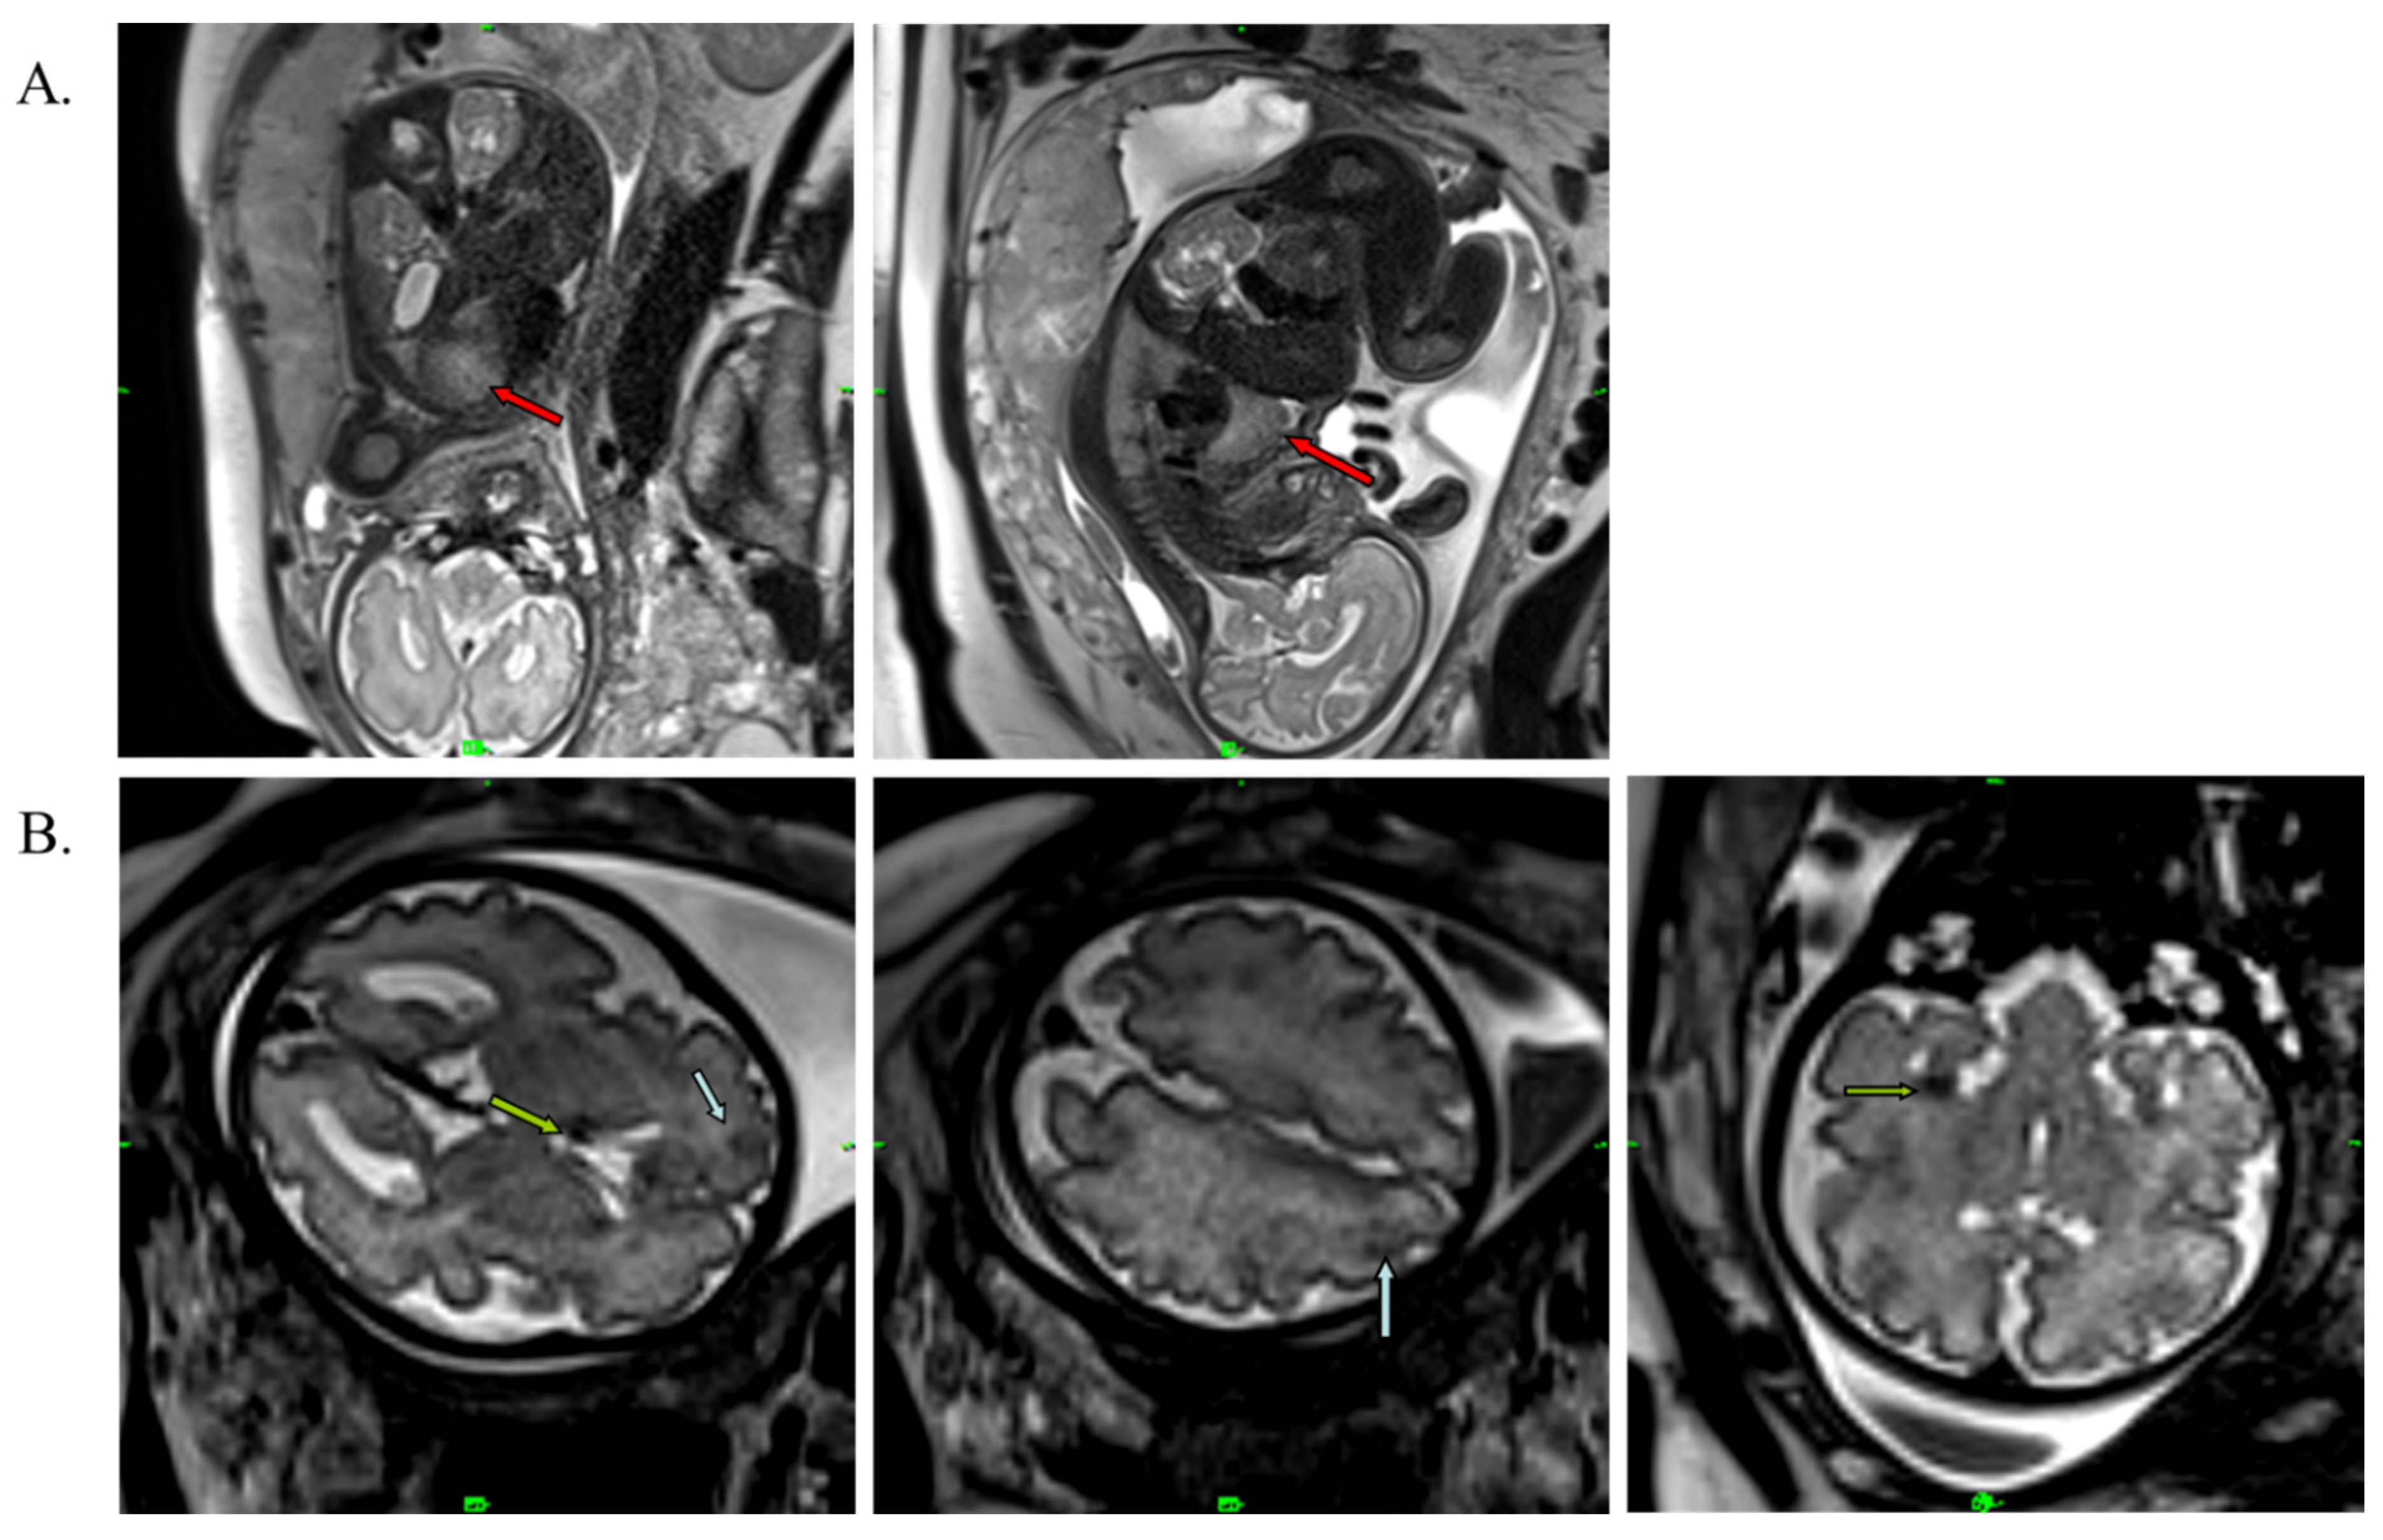

The male infant was born at term by caesarean section with a birth weight of 3700 g (+0.67 SD), birth length of 52 cm (+1.11 SD) and a head circumference of 35 cm (+0.42 SD). This was the mother’s fourth pregnancy (G3, P1). The Apgar score was 9/10. Standard deviations (SD) for birth measurements were calculated using WHO standards [30]. After birth, the boy was monitored in a perinatal intensive care unit for one week. His laboratory parameters were normal. Cardiological examination revealed rhabdomyoma and mitral insufficiency, and the abdominal ultrasound examination suggested angiomyolipoma in the kidneys. The MRI performed at 2 months of age confirmed the findings of the perinatal examinations (Figure 4A). The MRI additionally revealed white-matter radial migration lines, presenting a straight band and nonspecific conglomerate foci (Figure 4B).

Figure 4. T1-weighted axial MRI image of the brain and T2-weighted sagittal MRI image of the heart at 2 months of age. (A) Red arrows represent cardiac rhabdomyoma. (B) Blue arrows show cortical tubers in the sulcal island (1) and in the gyral core (2); green arrow represents a subependymal nodule. Brown and yellow arrows show white-matter radial migration lines: straight band (brown), nonspecific conglomerate foci (yellow).